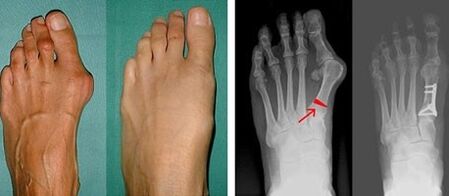

Ha a vizuális vizsgálat és a röntgensugarak nem adnak eredményt, akkor a beteget plantográfiára utalják, hogy meghatározzák a lehetséges lapos lábakat. Ez a módszer magában foglalja a láb lenyomatát, amely alapján ortopédiai tulajdonságokkal rendelkező cipőket vagy talpbetéteket készítenek a páciens számára. Ezután a betegnek podometriát írnak elő. Ez a módszer számítógépes elemzést használ a személy súlyának a lábra gyakorolt nyomásának meghatározására. A fejlett diagnosztika eredményei az első és második lábujj görbületének kezelési módszerének megválasztásának alapját képezik.

A nagylábujj és a kislábujj valgus azonosításának első szakaszában az orvos vizuális vizsgálatot végez. Ily módon meghatározza a patológia fejlődési szakaszát. Az ízületek részletes változásainak azonosítása érdekében röntgensugarakat és plantográfiát írnak elő.